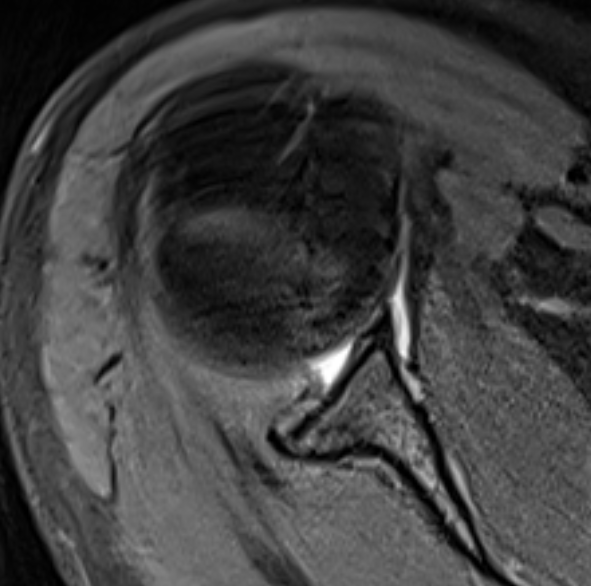

CT / MRI

Xray

Traction xray

- patient standing with 5-10 kg in each hand

- inferior subluxation of head